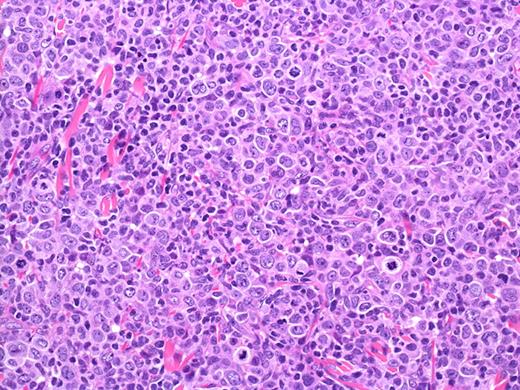

| Dense nodular dermal infiltrate composed of large pleomorphic, anaplastic, or immunoblastic cells with large, irregularly shaped nuclei and abundant pale or eosinophilic cytoplasm (Figure 5). Clusters of small reactive lymphocytes and eosinophils may be found within and surrounding the tumor cells. |

PCALCL: Cohesive sheets of anaplastic lymphoid cells H&E, original magnification ×200). The histologic photomicrograph was captured using a digital camera (AxioCam MRc5; Zeiss) mounted on an Olympus microscope (BX45; Olympus). Objective lens: 400×/0.75 NA. Imaging software: Axio Vision Release 4.8.2 (Zeiss) and Adobe Photoshop Version 8.0 (Adobe Systems Inc).